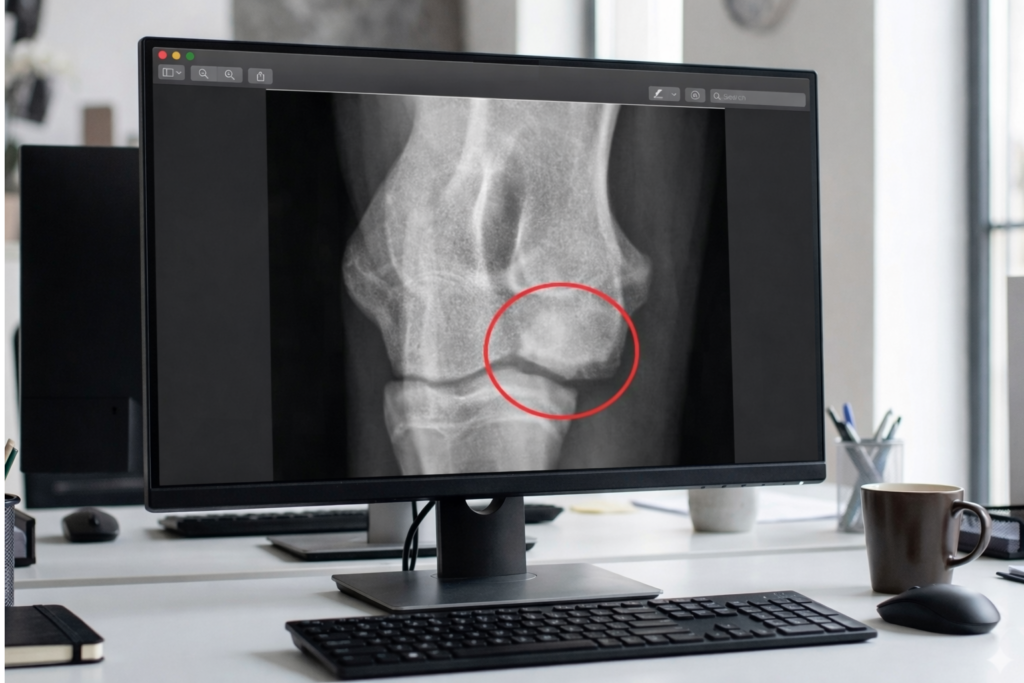

Isolierter Processus Anconeus

Bei dieser Form der ED ist ein Knochenfortsatz (Processus Anconaeus) der Elle im Rahmen des Wachstums nicht angewachsen (Störung in der Wachstumsfuge). Verschiedene Faktoren werden diskutiert. Die Verbindung zur Elle kann relativ fest oder gar nicht vorhanden sein. In jedem Fall kommt es jedoch durch den beweglichen Gelenkfortsatz zu einer andauernden Reizung des Gelenkes mit zügiger Bildung einer meist starken Arthrose. Die meisten Hunde lahmen deutlich und haben erhebliche Schmerzen im betroffenen Gelenk. Die Abbildung zeigt eine Röntgenaufnahme mit einem isoliertem Processus Anconeus im gekennzeichneten Kreis in dem die Verknöcherung nicht statt gefunden hat.